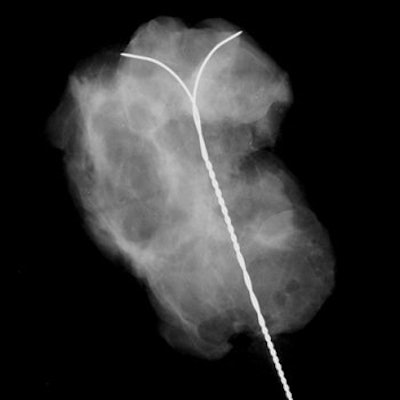

| Same patient as above. The MR study (axial plane) does not show any foci of enhancement. Bazzocchi M, Zuiani C, Panizza P, Del Frate C, Soldano F, Isola M, Sardanelli F, Giuseppetti GM, Simonetti G, Lattanzio V, Del Maschio A, "Contrast-Enhanced Breast MRI in Patients with Suspicious Microcalcifications on Mammography: Results of a Multicenter Trial" (AJR 2006; 186:1723-1732). |

Overall, the sensitivity of MRI was 87%, the specificity was 68%, the positive predictive value was 84%, the negative predictive value was 71%, and the accuracy was 80%.

"The not-perfect sensitivity of MRI -- 87% -- is a crucial point that prevents us from clinical use of MRI in the diagnosis of mammographically detected microcalcifications," the group wrote. "MRI cannot replace percutaneous or surgical biopsy, which gives pathological information."